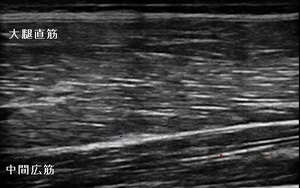

左大腿部 超音波長軸像 右同部 健(正常)側

圧痛と熱感が著明で、超音波観察を行ったところ、左大腿四頭筋のうち大腿直筋の近位で中間広筋との境界部で

肉離れを起こしている様子が認められました。(左上画像の丸の囲み)